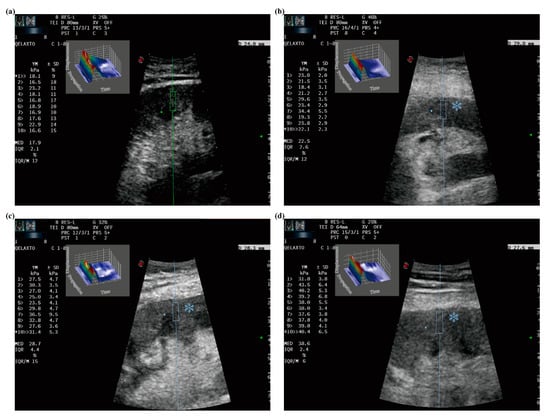

Figure 3. Measurements of p-SWE in renal transplants with different IF/TA stages: (a) IF/TA Grade 0, median = 17.9 kPa; (b) IF/TA Grade 1, median = 22.5 kPa; (c) IF/TA Grade 2, median = 28.7 kPa and (d) IF/TA Grade 3, median = 38.6 kPa. The line is used to drive operator to select suitable measurement areas. The square showed 3D eWave which is an exclusive tool that provides immediate feedback about the quality of the shear wave produced in the tissue, and is the three-dimensional representation of the shear waves generated by p-SWE. The asterisk showed the cooling indication (2 s in average) which is directly on the measurement site for “eye focus” feedback.

The p-SWE technique is characterized by the generation of the shear wave propagation to obtain tissue stiffness. Before the measurements, patients were suggested to practice breathing. During the p-SWE examinations, patients were required to hold their breath for approximately 3–4 s in a natural breathing state and lay in the supine position. To avoid the influence of probe pressure, the ultrasound transducer was placed vertically on the surface of the transplanted kidney and compressed slightly. A 5 mm × 10 mm region of interest (ROI) was placed in a parenchyma-area free of vessels in the p-SWE image. Ten repetitive and consecutive measurements (lasting 4–6 min) were performed in the same site. The median (M), interquartile range (IQR), and IQR/M of the elasticity values were automatically calculated and displayed. The median of 10 elasticity measurements in kilopascals was used for statistical analysis. Measurements were considered to fail when IQR/M was >30% (Figure 3).